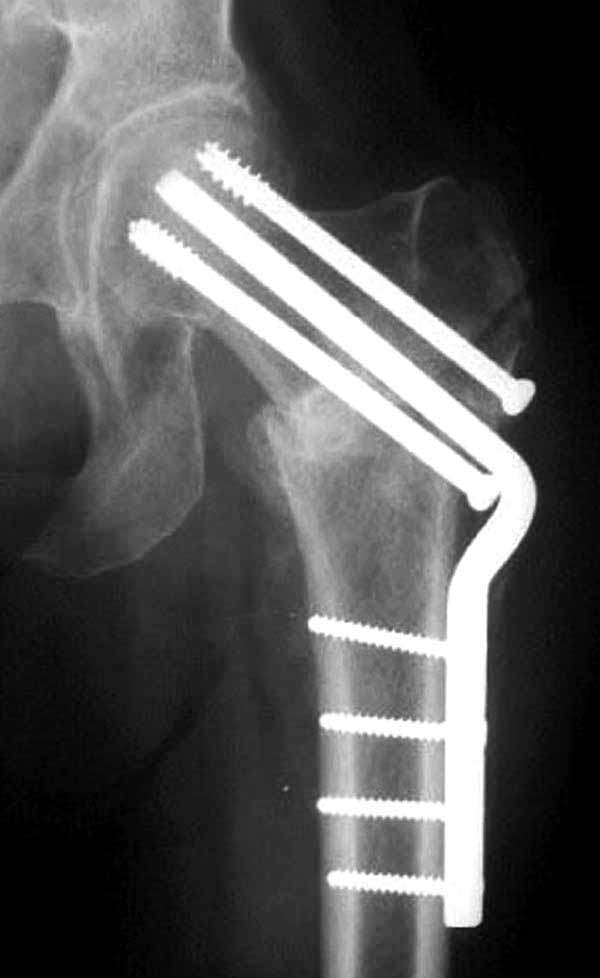

Здесь подобный случай, где стрессовый перелом обнаружен через 2 недели после фиксации. Применен Blade Plate с дополнительными шурупами.